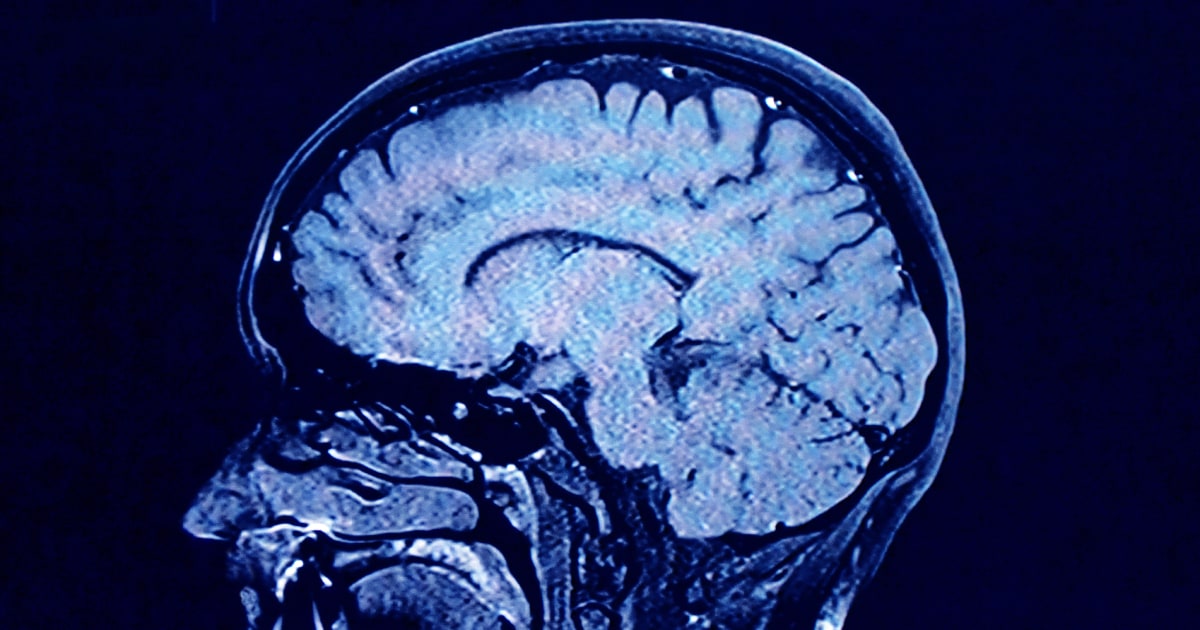

During each of these phases, our brains show markedly different characteristics in brain architecture, according to the new findings.

As we age, the human brain rewires itself. The process happens in distinct phases, or “epochs,” according to new research, as the structure of our neural networks changes and our brains reconfigure how we think and process information.

For the first time, scientists say they’ve identified four distinct turning points between those phases in an average brain: at ages 9, 32, 66 and 83. During each epoch between those years, our brains show markedly different characteristics in brain architecture, they say.

The findings, published Tuesday in the journal Nature Communications, suggest that human cognition does not simply increase with age until a peak, then decline. In fact, the phase from ages 9 to 32 is the only time in life when our neural networks are becoming increasingly efficient, according to the research.

During the adulthood phase, from 32 to 66, the average person’s brain architecture essentially stabilizes without major changes, at a time when researchers think people are generally plateauing in intelligence and personality.